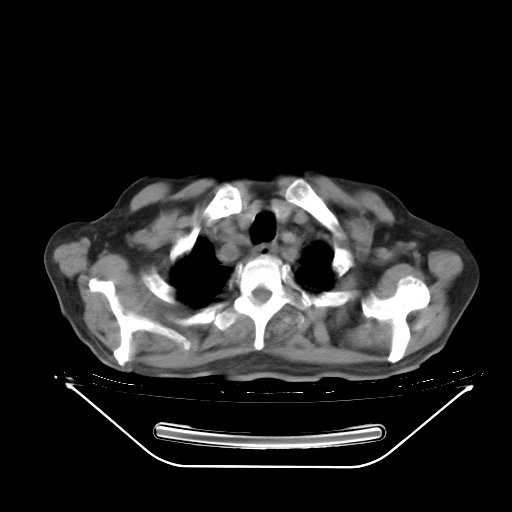

今天复查肺部CT,发现双肺广泛磨玻璃样改变。所以我把3月19日和5月9日相隔50天的肺部CT上传。请大家会诊。

5月9日肺部CT(在4月27日齐鲁医院肺部CT描述部分肺组织磨玻璃样改变,12天后肺组织广泛磨玻璃样改变)

2009年5月9日肺部CT